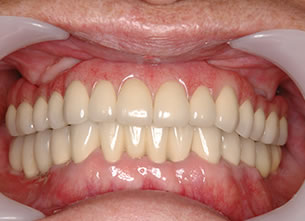

症例1 : 上下顎無菌顎症例

69歳、男性。

• 上顎は両側サイナスリフトと同時に即時荷重を行った。

• 下顎は抜歯即時埋入即時荷重を行った。

• 最終補綴物は、チタンのP.I.B.とM.B.のコンビネーションで修復した。

• 本症例の要旨は第39回日本口腔インプラント学会(大阪)にて症例報告した。